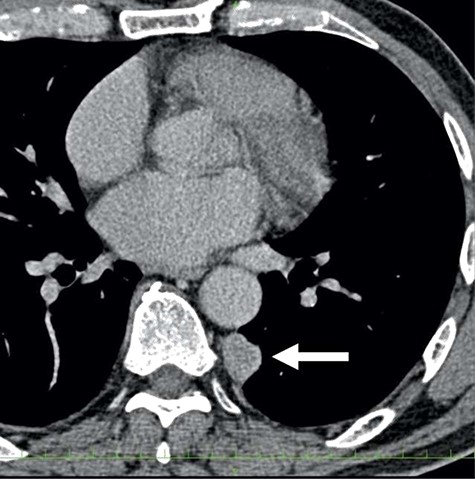

A 78-year-old man complained of chest pain for 2 months and was admitted to our hospital. Computed tomography (CT) scans revealed a tumor in the left thorax. He had undergone prior surgical resection of the primary SFT and recurrent tumor at 11 and 2 years before the current presentation. The CT findings of the primary tumor revealed a solitary, well-circumscribed and no signs of invasion (Fig. 1). Intraoperatively, the primary tumor arose from the visceral pleura and the resection was performed by wedge resection. The resected tumor was an oval, elastic soft mass with homogenous milky white cut surfaces. Postoperative histopathologic and immunohistochemical findings were consistent with SFT, and the mitosis and malignant features, including nuclear atypia, necrosis or higher cellularity, were hardly seen. In contrast to the primary tumor, as shown in Fig. 2, the CT findings revealed that the current tumor extended through the neural foramen. Furthermore, the tumor had an osteoclastic progression into the thoracic spine. Therefore, this tumor was considered to become malignant, and we considered the surgical complete resection is impossible. For histological confirmation, CT guided needle biopsy was performed. The histological findings of this recurrent tumor were identical to those of the primary tumor. The mitosis was hardly seen in this recurrent tumor. However, immunohistochemically, the MIB-1 proliferation index (Ki-67) of the primary tumor and the current tumor was 1.74 and 30.00%, respectively (Fig. 3A and B).

The computed tomographic findings of the primary tumor (arrow).